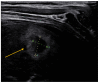

Point-of-care thoracic ultrasound at the patient's bedside has increased significantly recently, especially in pediatric settings. Its low cost, rapidity, simplicity, and repeatability make it a practical examination to guide diagnosis and treatment choices, especially in pediatric emergency departments. The fields of application of this innovative imaging method are many and include primarily the study of lungs but also that of the heart, diaphragm, and vessels. This manuscript aims to describe the most important evidence for using thoracic ultrasound in the pediatric emergency setting.